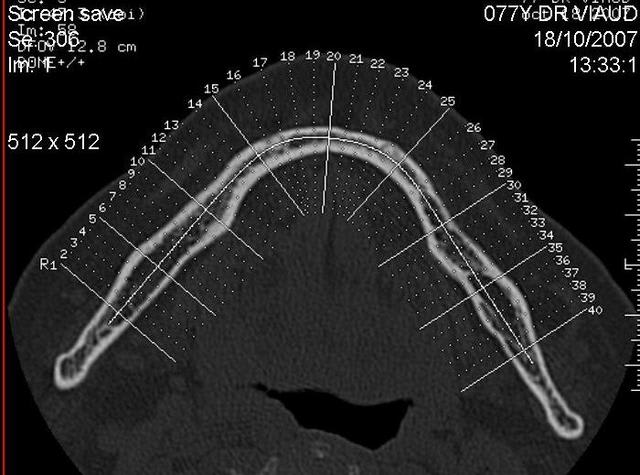

A mon avis tu peux mettre plus long mais surtout rester dans le bon axe et dans ton cas plus vestibulaire. Le danger c'est de perforer la partie linguale oùu effectivement ça peut être très grave (très très même!!). A la mandibule on doit faire des compromis sur l'émergence, les accastillages prothétiques nous permettent de rectifier des axes sans trop de risque. Voir ce cliché scanner d'un implant posé dans l'axe prothétique mais sans respecter l'axe osseux (il n'est pas de moi!), il a fallu le déposer...ce qui n'était pas le plus simple et en remettre un dans le bon axe. On est d'ailleurs souvent surpris en regardant des clichés sur implants au scanner.

A mon avis tu peux mettre plus long mais surtout rester dans le bon axe et dans ton cas plus vestibulaire. Le danger c'est de perforer la partie linguale où effectivement ça peut être très grave (très très même!!). A la mandibule on doit faire des compromis sur l'émergence, les accastillages prothétiques nous permettent de rectifier des axes sans trop de risque. Voir ce cliché scanner d'un implant posé dans l'axe prothétique mais sans respecter l'axe osseux (il n'est pas de moi!), il a fallu le déposer...ce qui n'était pas le plus simple et en remettre un dans le bon axe. On est d'ailleurs souvent surpris en regardant des clichés sur implants au scanner.

Exemple type où sans forets, mis à part l’initial de 0.7mm les condenseurs sont « guidés par la corticale et évitent le mauvais axe, même si en vestibulaire c’est moins grave qu’en lingual